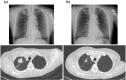

Epidermal growth factor receptor (EGFR) tyrosine kinase inhibitors (TKIs) are common therapeutic agents for EGFR mutation-positive advanced non-small-cell lung cancer. There has been no report of rhabdomyolysis caused by an overdose of EGFR-TKIs. We herein review the existing literature on the subject and report a rare case of rhabdomyolysis due to an overdose of gefitinib, an EGFR-TKI.